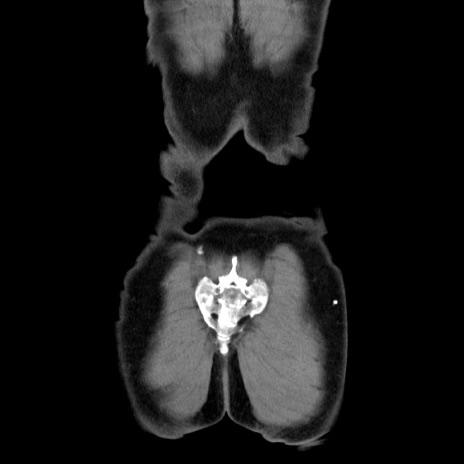

症例34(冠状断像)

【身体所見】右鼠径部に小児頭大の膨隆あり。弾性硬であり、用手還納は困難。左鼠径部にも膨隆を認める。脱出はなし。